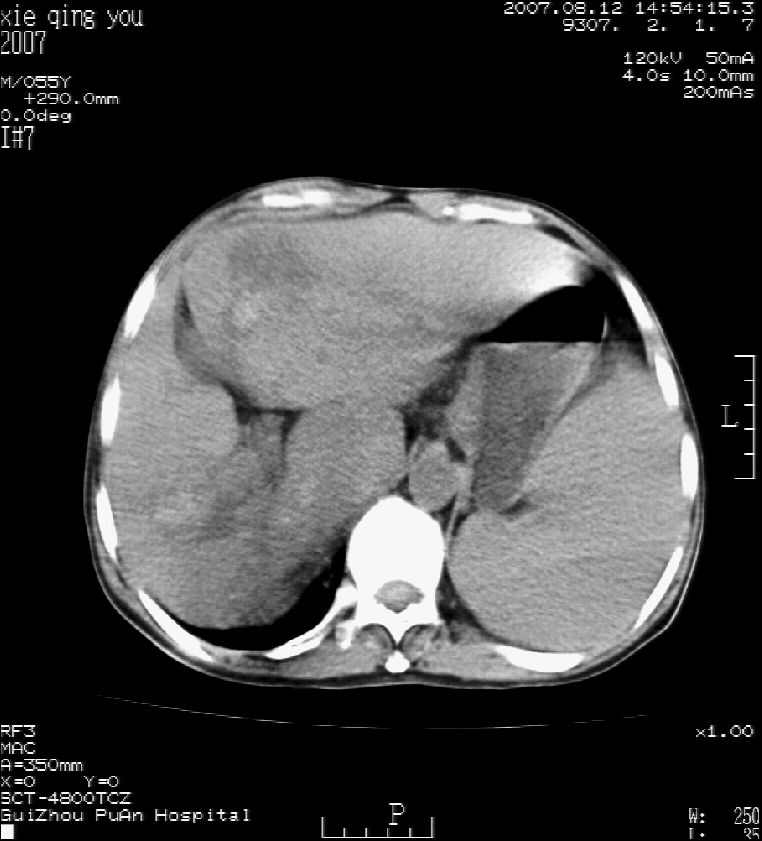

男 55岁  反复上腹痛1年,伴恶心呕吐。2005年做第一次检查后,到外院做b超检查提示肝囊肿,未做任何手术。2006年做过胆总管结石术。骨窗未见异常

2007年8月片